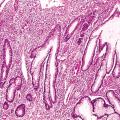

Carcinome épidermoïde de la marge anale

CARCINOME EPIDERMOIDE